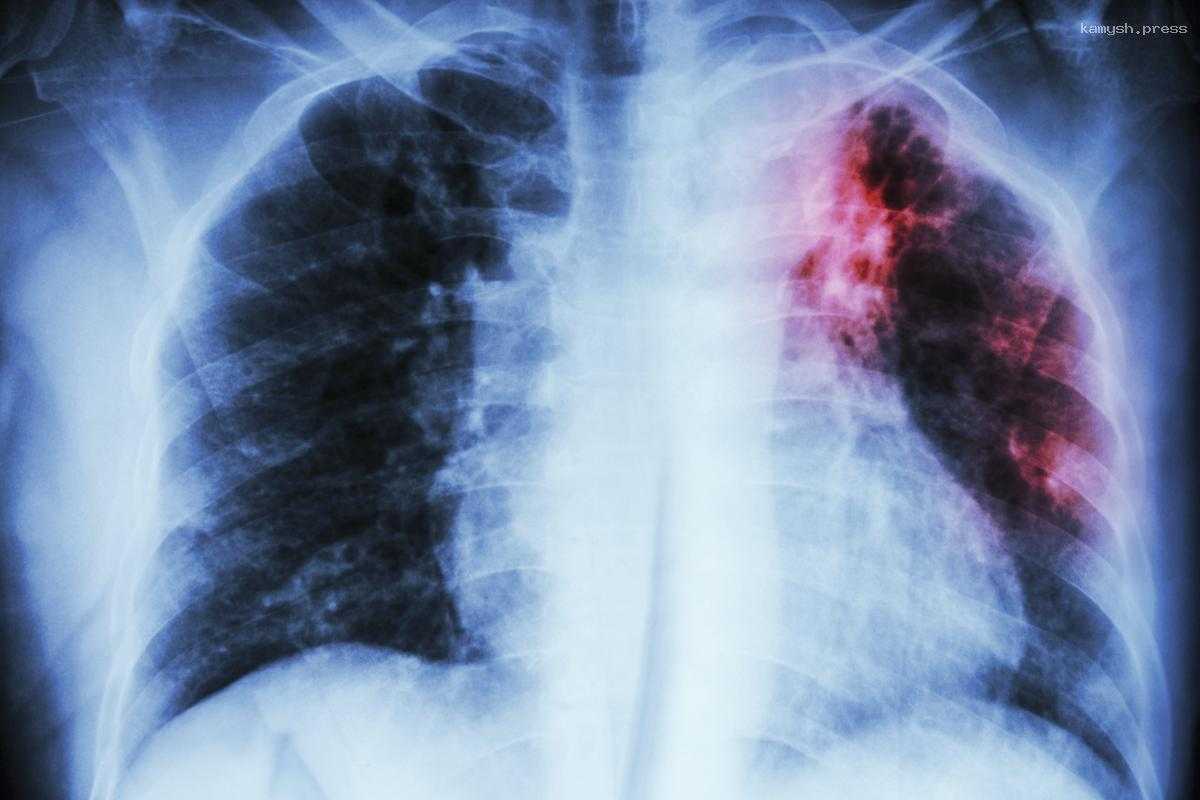

Сотрудница пищеблока с ВИЧ-положительным статусом заразила десятки детей в школе туберкулезом

Согласно информации из Telegram-канала, у женщины был диагностирован туберкулез в 2005 году, а ВИЧ – в 2019-м. Однако, несмотря на эти обстоятельства, она была допущена к работе после медицинского осмотра в конце 2022 года.